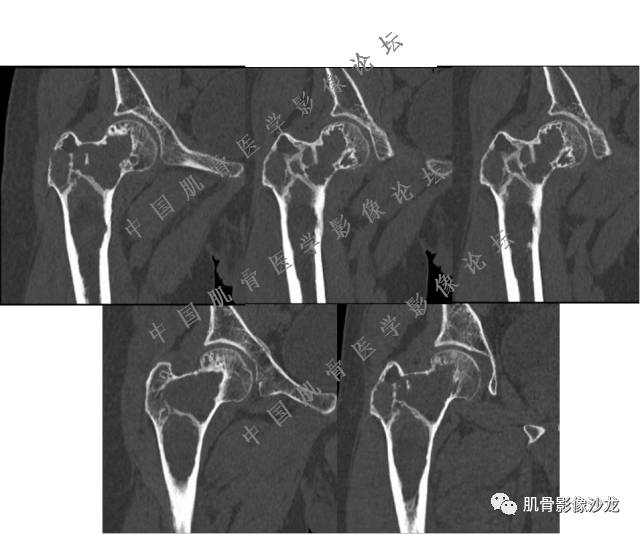

葛英霖 20:10 判断恶性程度需要看骨髓内浸润的是肿瘤还是水肿 ,从目前看,骨肉瘤是要考虑的

张小林 20:13 磁共振有双低信号,结合CT确实要考虑有纤维成份。

医影在线 20:13 干骺端溶骨性破坏,边缘模糊,低密度肿块,似有钙化

Echo 20:13 有骨质破坏,边界不清,有软组织肿块,我觉得恶性是要考虑的

Echo 20:16 软组织肿块突破了骨皮质

葛英霖 20:20 局部骨质有硬化,不能完全排除干扰

张小林 20:23 富含巨细胞骨肉瘤?

Echo 20:23 我个人觉得,17岁男性,病灶发生在原干骺端区域,溶骨性骨质破坏,似有肿瘤骨,有软组织肿块形成,从常见病发生率来说,骨肉瘤还是要考虑的

葛英霖 20:24 这个部位有一个需要鉴别的就是软骨母